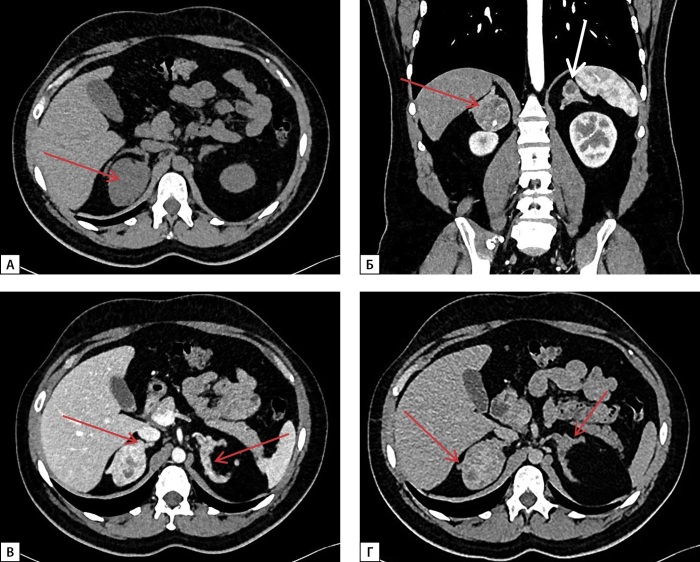

先天性肾上腺增生症(CAH)包括一组常染色体隐性遗传病,其特征是类固醇生成关键酶缺陷,其中CYP21A2基因突变导致的21-羟化酶缺乏症是最常见的形式。自从20世纪50年代引入替代疗法和新生儿筛查项目以来,诊断为CAH的新生儿的存活率显著增加。然而,尽管取得了这些进展,与这种疾病相关的死亡率仍然高得不成比例。通过药物治疗获得最佳治疗补偿仍然是一个复杂的挑战,导致一系列长期并发症。这些并发症源于潜在疾病及其治疗,影响关键的生理功能,包括代谢、生长发育、心血管健康和生育能力。这些多方面的结果强调了持续研究和改进治疗方法以更好地管理这一复杂疾病的必要性。这篇文章提出了一系列的四个临床病例CAH的特点是缺乏持续补偿糖和矿皮质激素缺乏。这些病例因大肾上腺肿块和异位睾丸肾上腺休息组织(TART)的发展而进一步复杂化,强调了实现长期疾病管理的挑战。

Congenital adrenal hyperplasia (CAH) encompasses a group of autosomal recessive disorders characterized by defects in enzymes critical for steroidogenesis, with 21-hydroxylase deficiency due to mutations in the CYP21A2 gene being the most prevalent form.Since the introduction of replacement therapy and neonatal screening programs in the 1950s, there has been a significant increase in survival rates among newborns diagnosed with CAH. However, despite these advancements, mortality associated with this condition remains disproportionately high. Achieving optimal therapeutic compensation through medication remains a complex challenge, contributing to a range of long-term complications. These complications stem from both the underlying disease and its treatment, impacting key physiological functions, including metabolism, growth and development, cardiovascular health, and fertility. These multifaceted outcomes underscore the need for ongoing research and the refinement of therapeutic approaches to better manage this intricate condition. This article presents a series of four clinical cases of CAH characterized by the absence of sustained compensation for glucoand mineralocorticoid deficiencies. These cases were further complicated by the development of large adrenal masses and ectopic testicular adrenal rest tissue (TART), emphasizing the challenges in achieving long-term disease management.